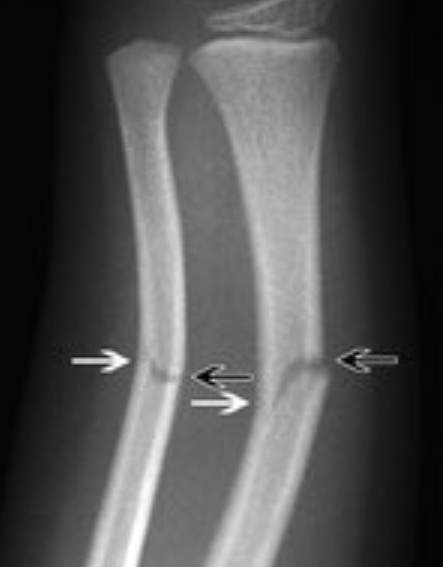

في المواضع الأخرى، قوة التعديل الذاتي التي تجعل الطبيب المتخصص يقبل وضعية بعض الكسور رغم سوئها الظاهر تجعل بعض الوالدين قلقين من صور الأشعة لعدم استيعابهم لهذه الظاهرة . لذلك أرى أن عرض مثل هذه الصور التي تظهر هذه الظاهرة هو الوسيلة الأمثل لطمأنة الوالدين ..

ليونة عظم الطفل تجعله ينحني أحيانا كما ينحني الغصن الأخضر قبل أن ينكسر ...

الكسور الغير كاملة (ما يسمى في العامية الشَّعر) شائعة جدا ضمن كسور الأطفال وذلك لمرونة عظم الطفل الذي قد يكسر من جهة ويبقى متصلا من الأخرى…

يطلق الأطباء لقب "كسر الغصن الأخضر" على هذا النوع من كسور الأطفال الذي تنكسر فيه جهة من العظم وتبقى الأخرى سليمة وهو تشبيه دقيق …